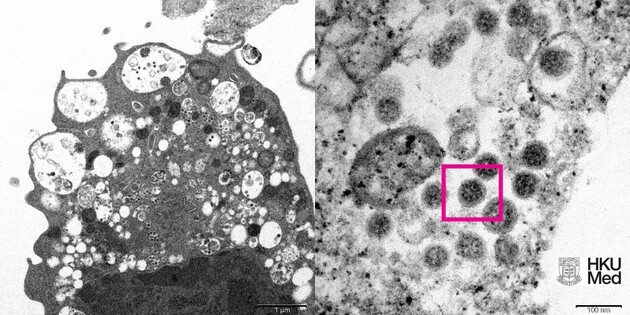

“Данные, собранные за последние недели, подтверждают, что „омикрон“ обладает высокой степенью заразности, поскольку мутации, которые он содержит, позволяют вирусу легче прикрепляться к клеткам человека, и он может заразить даже тех, кто ранее был инфицирован или вакцинирован”, — сказал Клюге.